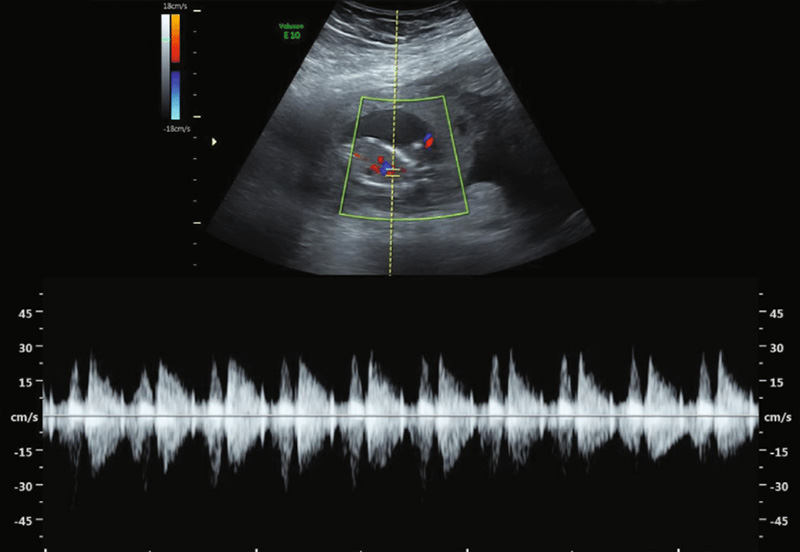

تپش قلب جنین در هفتههای ابتدایی بارداری با استفاده از سونوگرافی قابل شناسایی است

پزشکان معمولاً از هفته هفتم تا هشتم بارداری میتوانند صدای تپش قلب را تشخیص دهند. این صدا به دلیل انقباضات قلب و پمپاژ خون به وجود میآید و به عنوان یک نشانه مثبت از سلامت جنین و پیشرفت طبیعی بارداری محسوب میشود.

صدای قلب جنین معمولاً شبیه به یک تپش منظم و ریتمیک است که به راحتی قابل شنیدن است. این صدا به طور معمول بین ۱۲۰ تا ۱۶۰ ضربه در دقیقه متغیر است. در این مرحله، تپش قلب جنین به وضوح نشاندهنده فعالیتهای حیاتی اوست و والدین با شنیدن این صدا احساس آرامش و نزدیکی بیشتری با فرزند خود پیدا میکنند.

در طول بارداری، نظارت بر تپش قلب جنین یکی از بخشهای مهم مراقبتهای دوران بارداری است. پزشکان با دقت تغییرات در ریتم یا شدت تپش قلب را تحت نظر دارند، زیرا این تغییرات میتوانند نشانهای از مشکلات احتمالی باشند. همچنین، در برخی موارد، پزشکان از دستگاههای خاصی برای نظارت مداوم بر تپش قلب جنین استفاده میکنند.